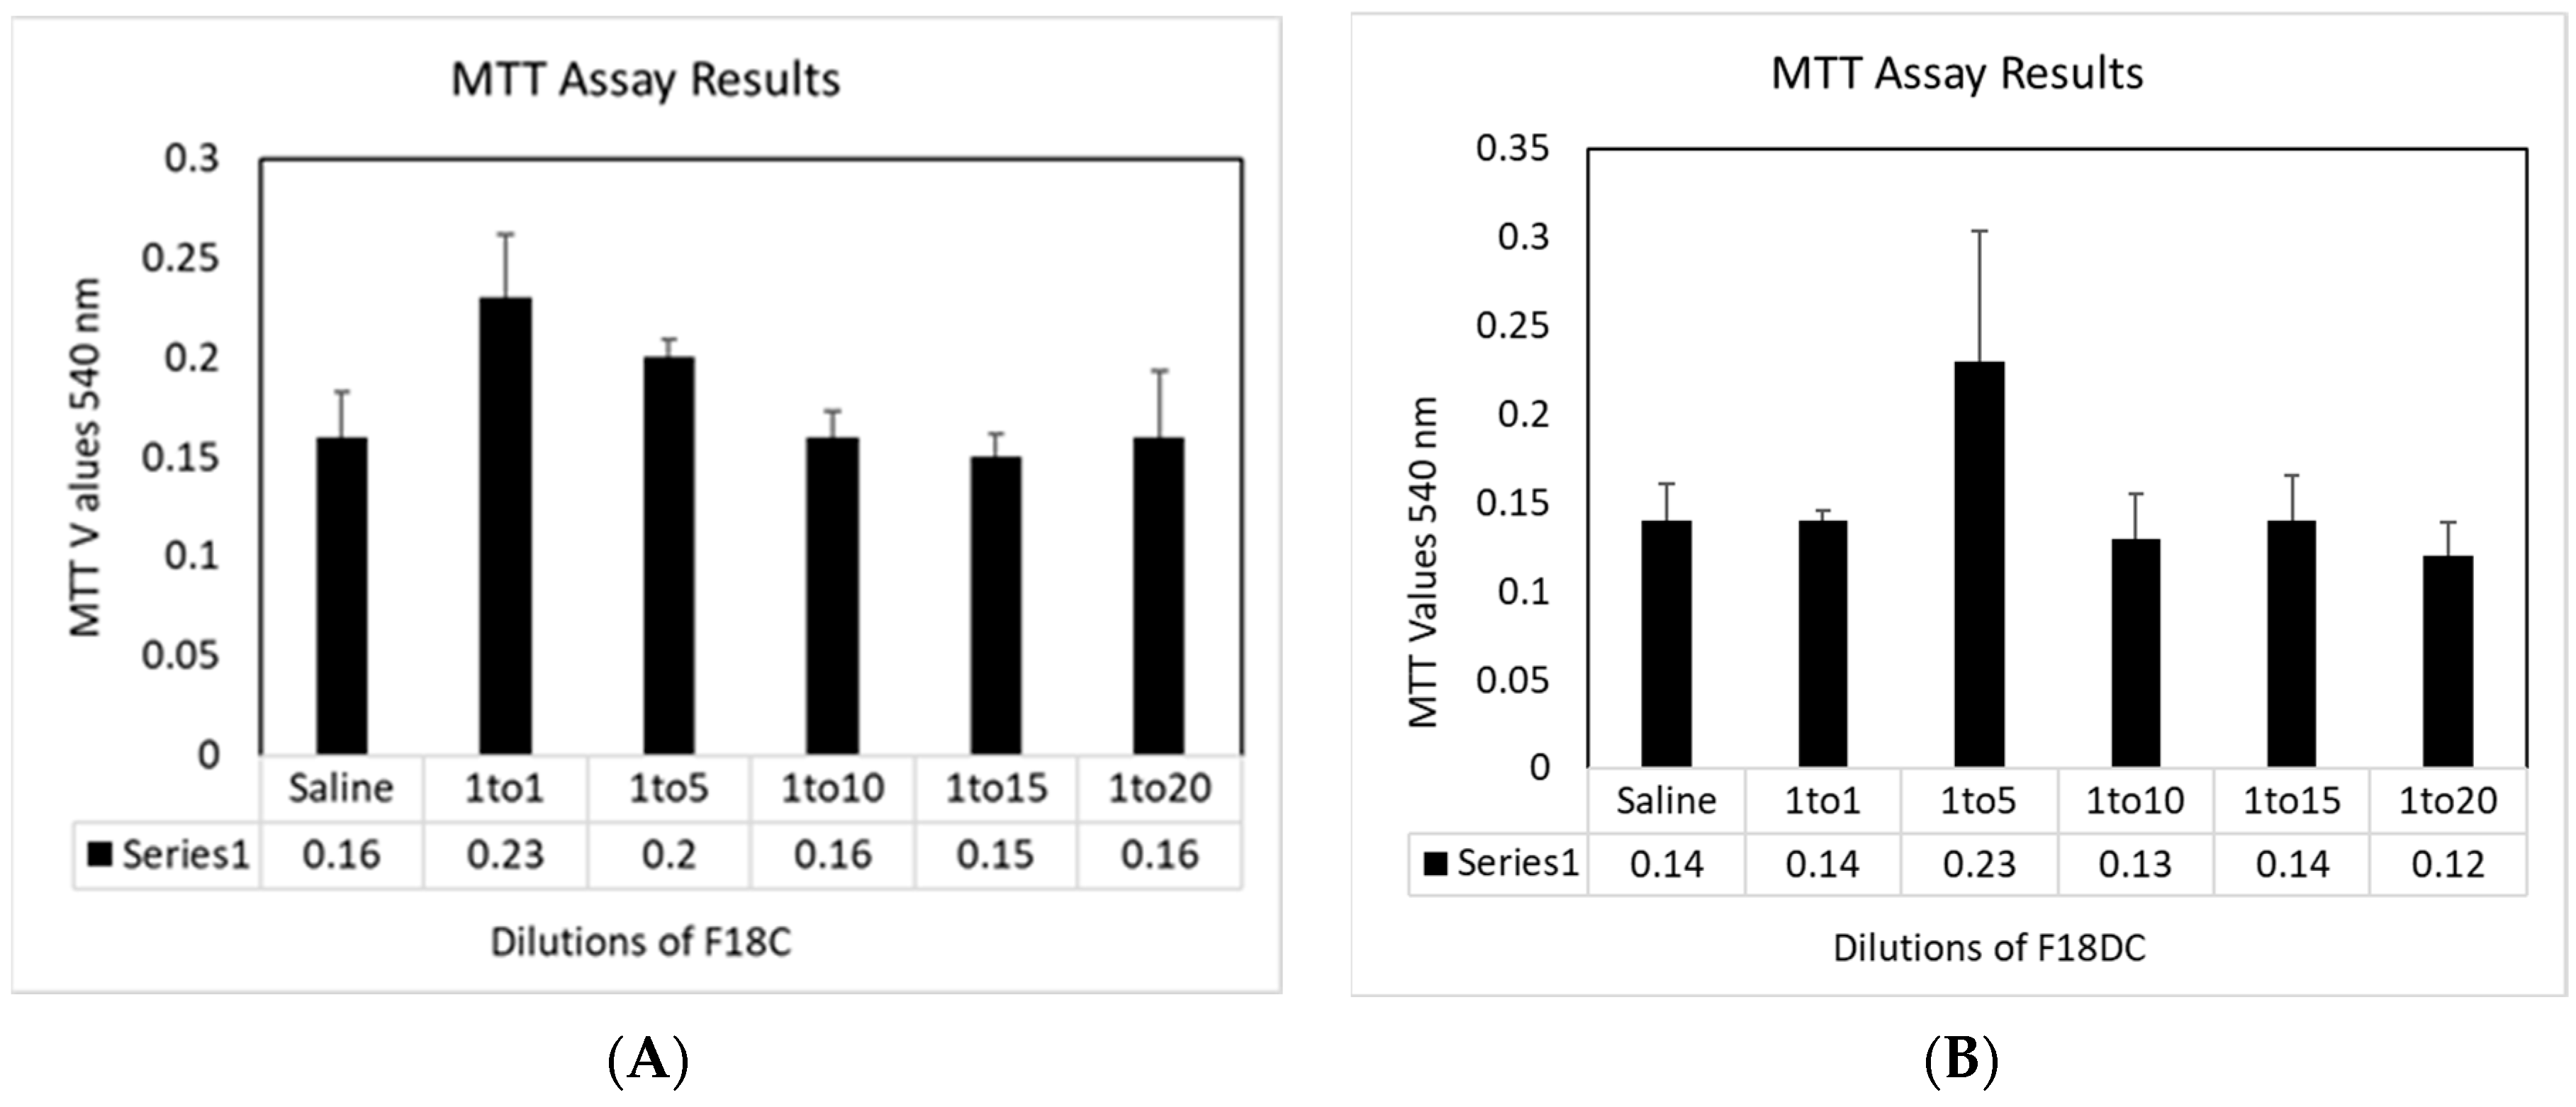

3.4. Cytotoxicity towards HNpEC Cells Measured by MTT Cell Viability Assay